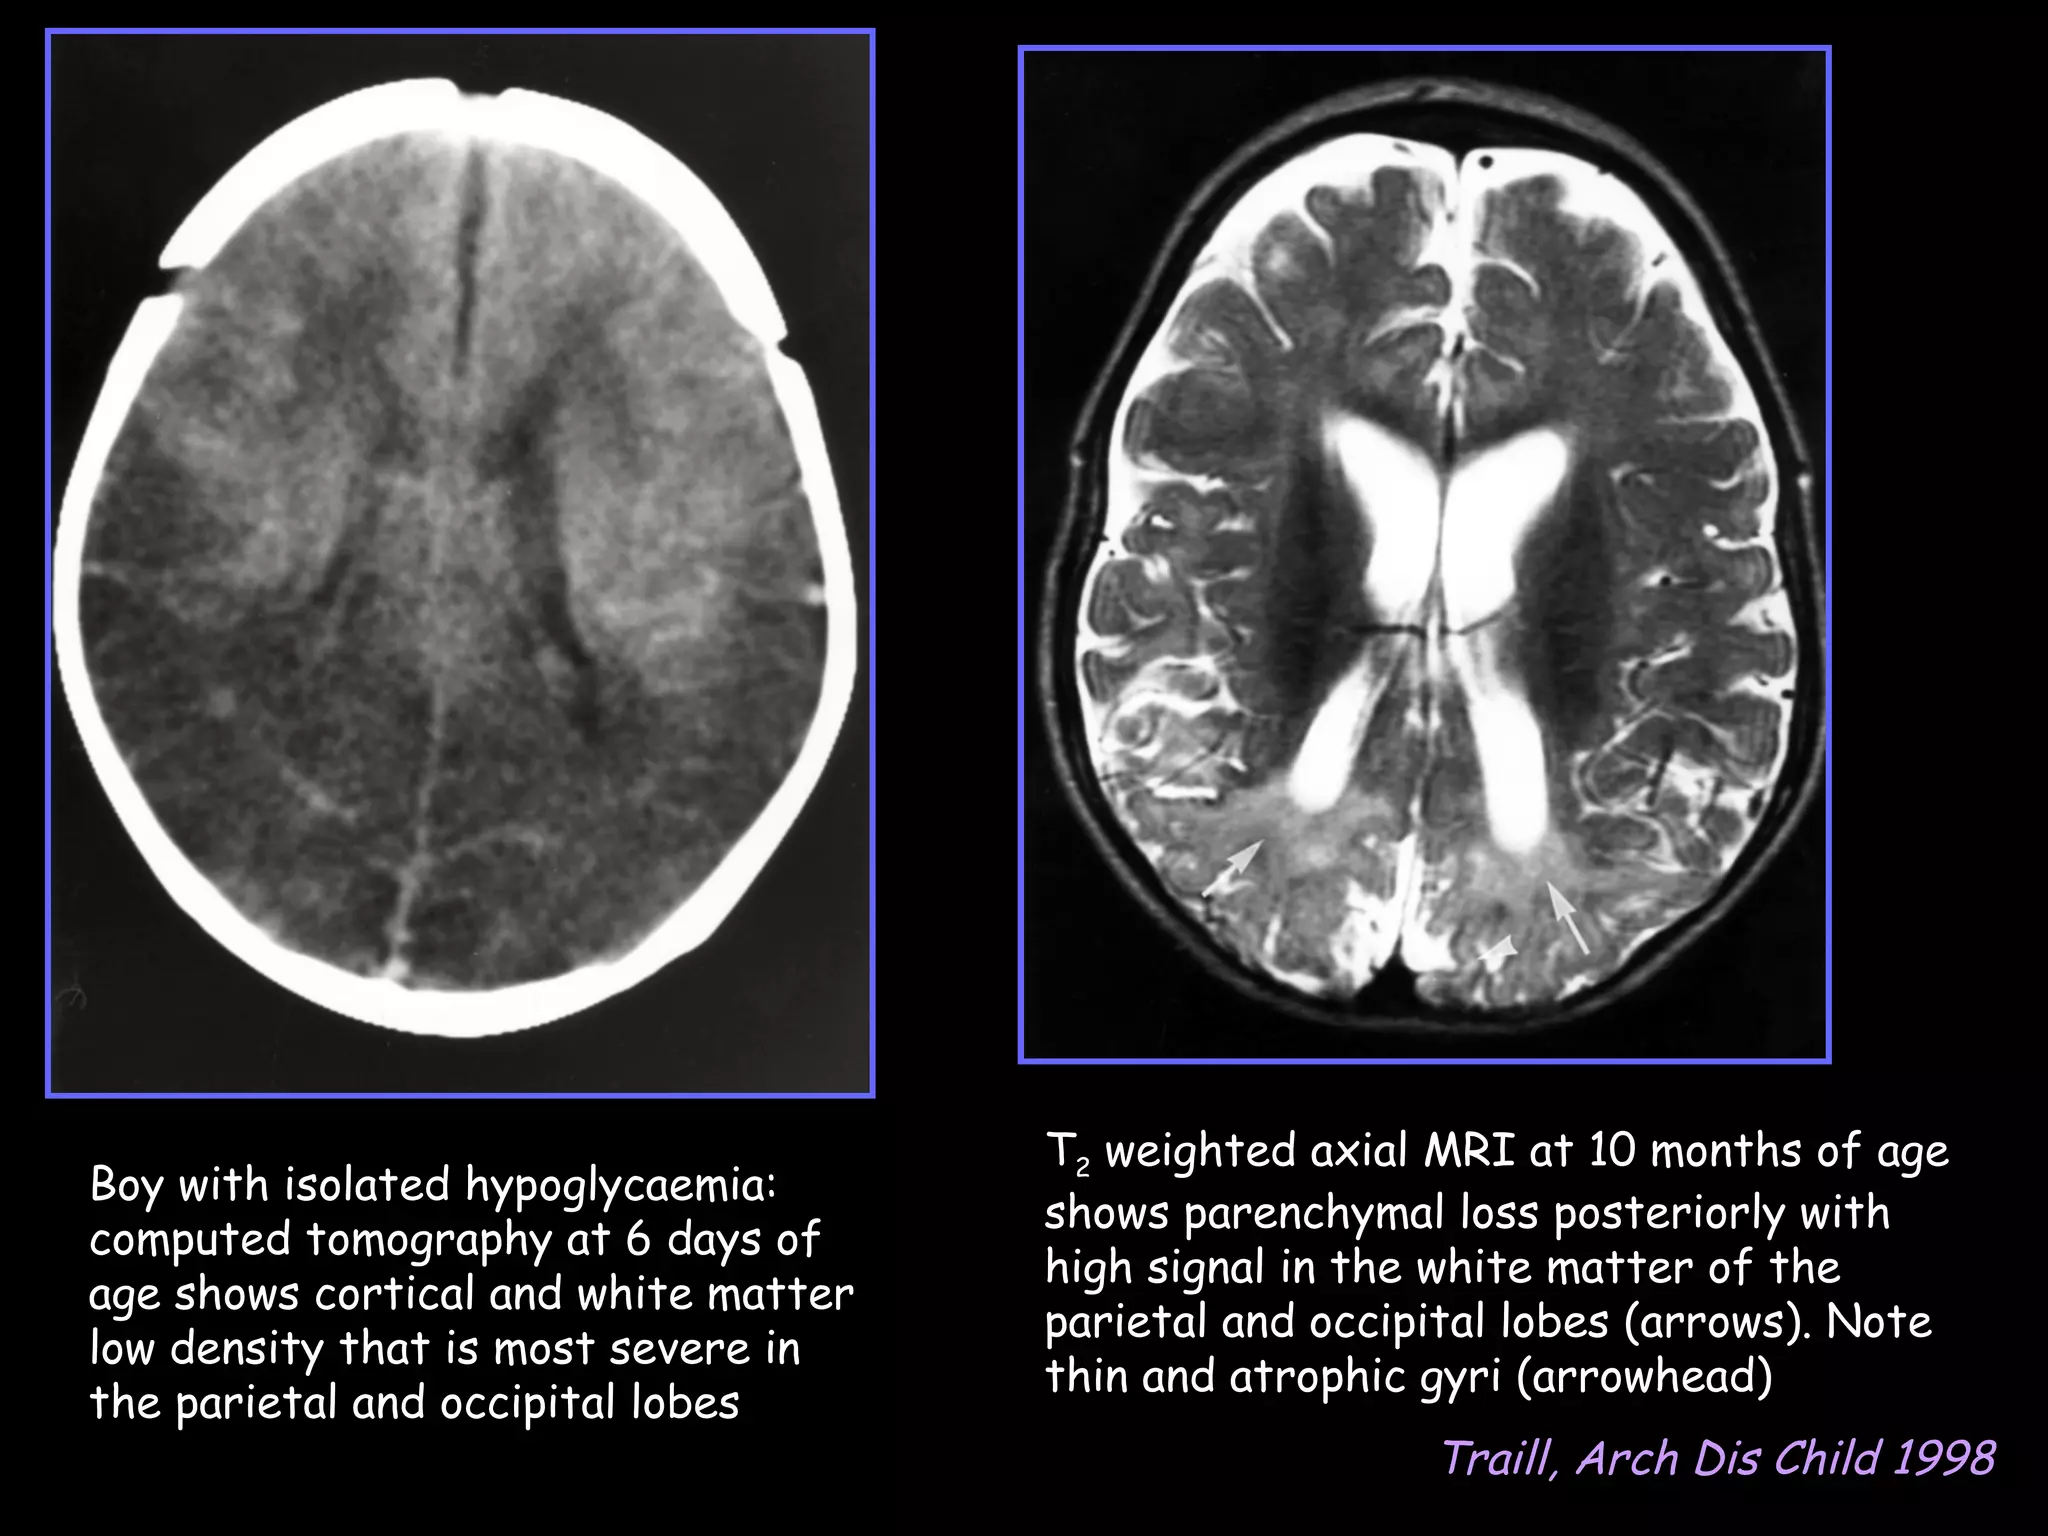

T2 weighted axial MRI at 10 months of age

Boy with isolated hypoglycaemia:

shows parenchymal loss posteriorly with

computed tomography at 6 days of

high signal in the white matter of the

age shows cortical and white matter

parietal and occipital lobes (arrows). Note

low density that is most severe in

thin and atrophic gyri (arrowhead)

the parietal and occipital lobes

Traill, Arch Dis Child 1998

T2 weighted axialMRI at 10 months of age Boy with isolated hypoglycaemia: shows parenchymal loss posteriorly with computed tomography at 6 days of high signal in the white matter of the age shows cortical and white matter parietal and occipital lobes (arrows). Note low density that is most severe in thin and atrophic gyri (arrowhead) the parietal and occipital lobes Traill, Arch Dis Child 1998